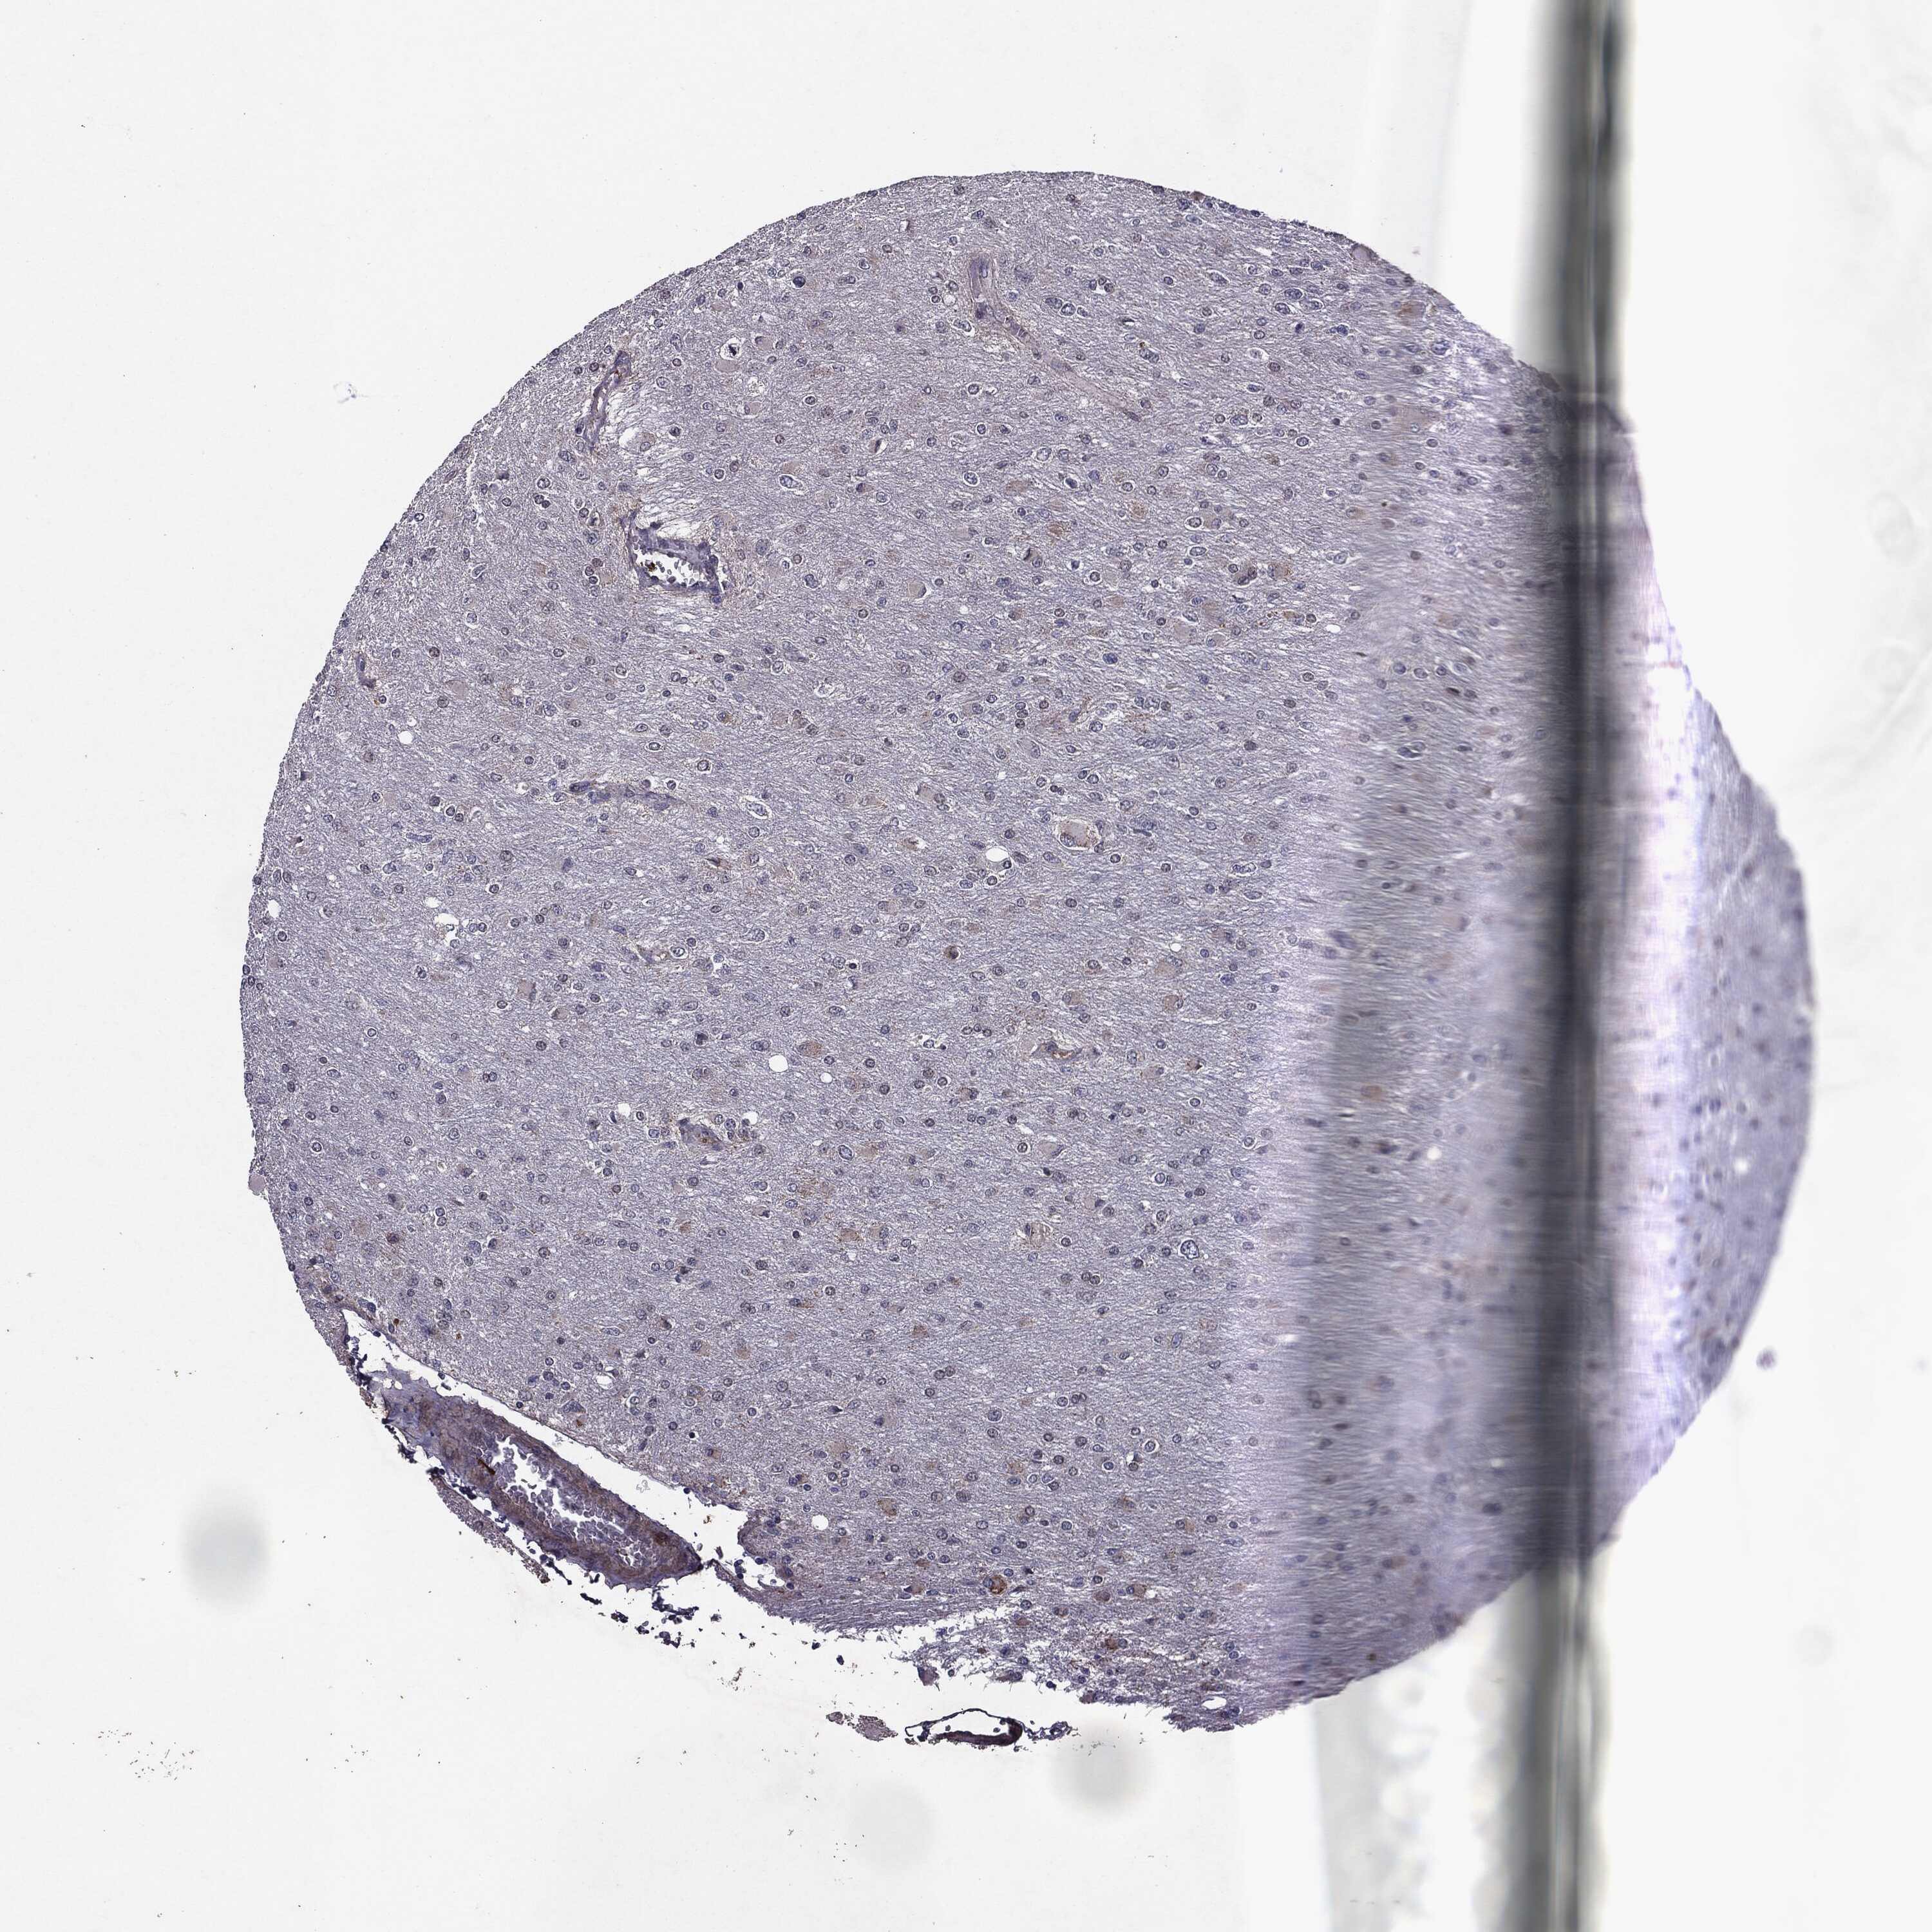

GLIOMA - Protein expressioni

A mouse-over function shows sample information and annotation data. Click on an image to view it in a full screen mode. Samples can be filtered based on level of antibody staining by selecting one or several of the following categories: high, medium, low and not detected. The assay and annotation is described here.

Note that samples used for immunohistochemistry by the Human Protein Atlas do not correspond to samples in the TCGA dataset.

Antibody stainingi

Antibody staining in the annotated cell types in the current human tissue is reported as not detected, low, medium, or high, based on conventional immunohistochemistry profiling in selected tissues. This score is based on the combination of the staining intensity and fraction of stained cells.

Each image is clickable and will lead to virtual microscopy that enables deeper exploration of all samples and also displays staining intensity scores, fraction scores and subcellular localization as well as patient and tissue information for each sample.

Antibody HPA052606

Antibody HPA077139

Staining

High

Medium

Low

Not detected

Intensity

Strong

Moderate

Weak

Negative

Quantity

>75%

75%-25%

<25%

None

Location

Nuclear

Cytoplasmic/membranous

Cytoplasmic/membranous,nuclear

Glioma, malignant, Low grade

Glioma, malignant, High grade

Glioma, malignant, NOS